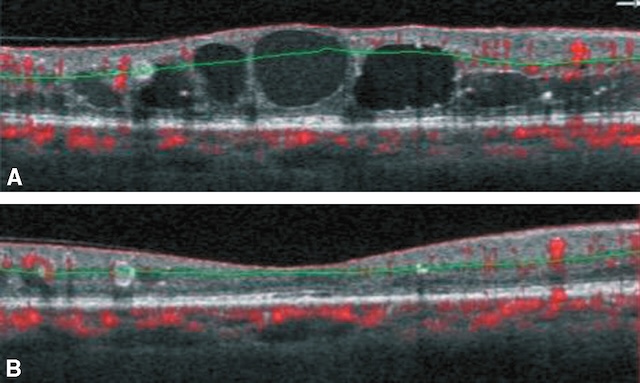

Fig. 20.10 A. Retinopathie diabétique proliférante avec fibrose prérétinienne (flèche bleue). B. Décollement de rétine tractionnel (flèche rouges), bien visible en OCT. Sur l’image A, un fond d’œil révèle une rétinopathie diabétique proliférante marquée par une fibrose prérétinienne épaisse et blanchâtre s’étendant en arc autour de la papille et de la macula. La traction générée par ces membranes fibrovasculaires est évidente, avec des plis rétiniens radiaires et un soulèvement localisé de la rétine. L’image B, en OCT, confirme un décollement de rétine de type tractionnel : la rétine est soulevée sans espace sous-rétinien liquidien net, et les insertions des tractions sont visibles de part et d’autre, souvent à proximité des néovaisseaux. L’ensemble témoigne d’un stade avancé de complication diabétique nécessitant une prise en charge chirurgicale.

Des injections d’anti-VEGF (ranibizumab, aflibercept) sont efficaces pour réduire l’œdème maculaire et maintenir ou améliorer l’acuité visuelle durant de nombreux mois. Ce traitement est indiqué en cas d’œdème atteignant le centre de la macula et associé à une baisse de l’acuité visuelle (fig. 20.16).

Noter la disparition des espaces microkystiques et le retour à un profil maculaire proche de la normale.

L’image A en tomographie en cohérence optique (OCT) révèle un œdème maculaire cystoïde typique, avec plusieurs cavités hypo-réflectives bien délimitées dans l’épaisseur de la rétine centrale, traduisant une accumulation de liquide intrarétinien. Les contours fovéolaires sont bombés, et l’épaississement rétinien est net. En B, un mois après l’injection intravitréenne d’un anti-VEGF, la rétine apparaît nettement asséchée. Les espaces kystiques ont disparu, la fovéa retrouve une configuration concave normale, et l’épaisseur rétinienne est considérablement réduite. Cette évolution témoigne d’une réponse favorable au traitement avec une résorption quasi complète du liquide.